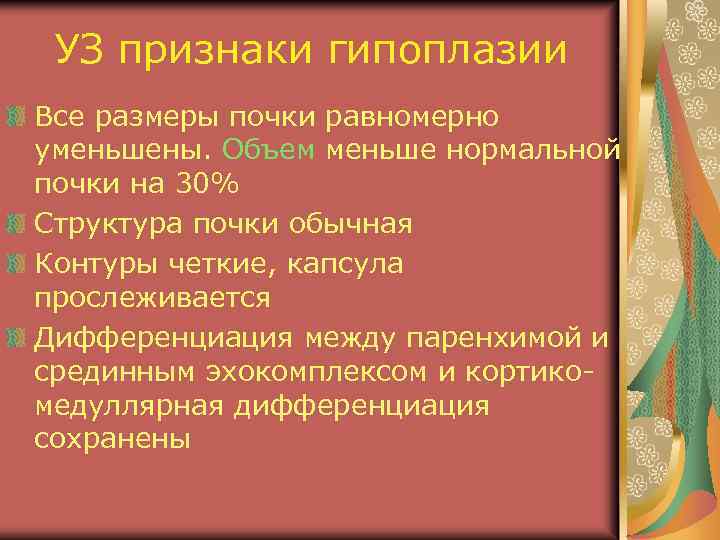

УЗ признаки гипоплазии Все размеры почки равномерно уменьшены. Объем меньше нормальной почки на 30% Структура почки обычная Контуры четкие, капсула прослеживается Дифференциация между паренхимой и срединным эхокомплексом и кортикомедуллярная дифференциация сохранены